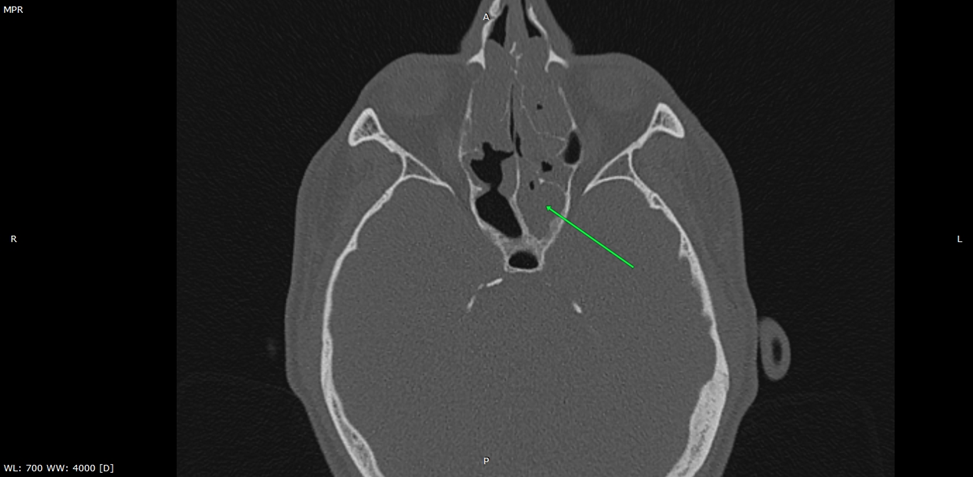

КТ ППН аксиальный срез. Соустья верхнечелюстных пазух расширены. Состояние после удаления крючковидных отростков

Левая: слизистая диффузно утолщена до 5 мм, преимущественно в альвеолярных отделах. Гайморо-назальное соустье расширено (состояние после резекции крючковидного отростка). Просвет соустья обтурирован мягкотканным образованием плотность +10...+50 HU.

Правая: слизистая диффузно утолщена до 5 мм, преимущественно в альвеолярных отделах. Гайморо-назальное соустье проходимо, расширено (состояние после резекции крючковидного отростка).